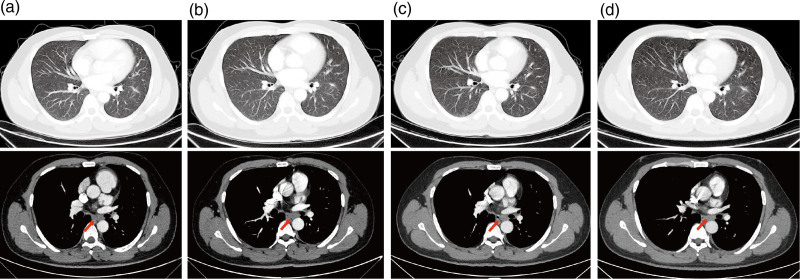

The novel and highly selective anaplastic lymphoma kinase ( ALK ) inhibitor iruplinalkib showed potent activity and manageable safety profiles in patients with ALK -rearranged non-small cell lung cancer (NSCLC). However, the evidence of iruplinalkib for uncommon ALK double fusion and secondary G1202R resistance mutation is limited. Here, we report a case of a 36-year-old male with metastatic NSCLC harboring uncommon TTC7A - ALK and EML4 - ALK double fusion. Alectinib as first-line therapy showed partial response, with a progression-free survival (PFS) of 20 months. When his disease progressed, the ALK secondary G1202R resistance mutation was identified. His metastatic paraesophageal lymph node decreased during iruplinalkib treatment, achieving an ongoing PFS benefit for 10 months. Treatment-related adverse events of iruplinalkib were grade 1 hypercholesterolemia and hypertriglyceridemia. The modeling simulation revealed that the G1202R mutation exerted little effect on the binding of iruplinalkib. Iruplinalkib showed potency to G1202R because of its unique chemical structure and removal of steric clashes, which might be a promising option for ALK -rearranged NSCLC patients with G1202R resistance mutation.